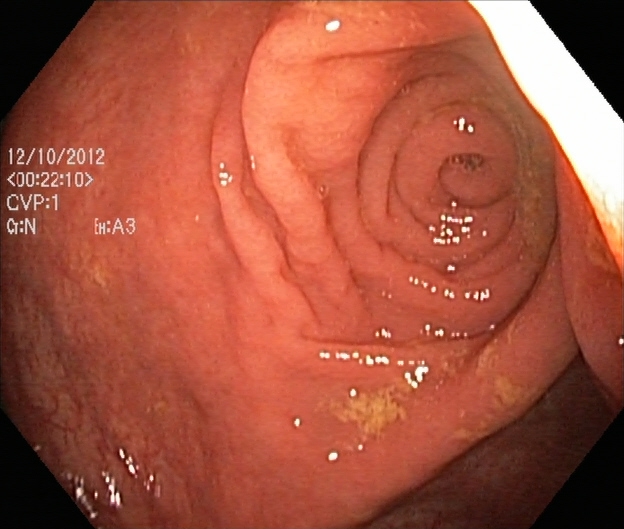

An automatic and efficient Computer-Aided Diagnosis (CAD) system in a clinic could assist medical experts during the endoscopic and colonoscopy procedure to improve the detection rate by finding unrecognized lesions and act as a second observer by providing better insights to the gastroenterologist concerning the presence and types of lesions. With this inspiration, we conducted five experiments to classify 161616 classes of GI tract conditions for the Medico Multimedia Task at MediaEval 2018 (Pogorelov et al., 2018b). One example for each of the 16 classes is depicted in Figure 1.

Figure 1. Sample images of GI findings. Each image represents one of the 16 classes from the dataset used for the Medico 2018 challenge (Pogorelov et al., 2017c, a).